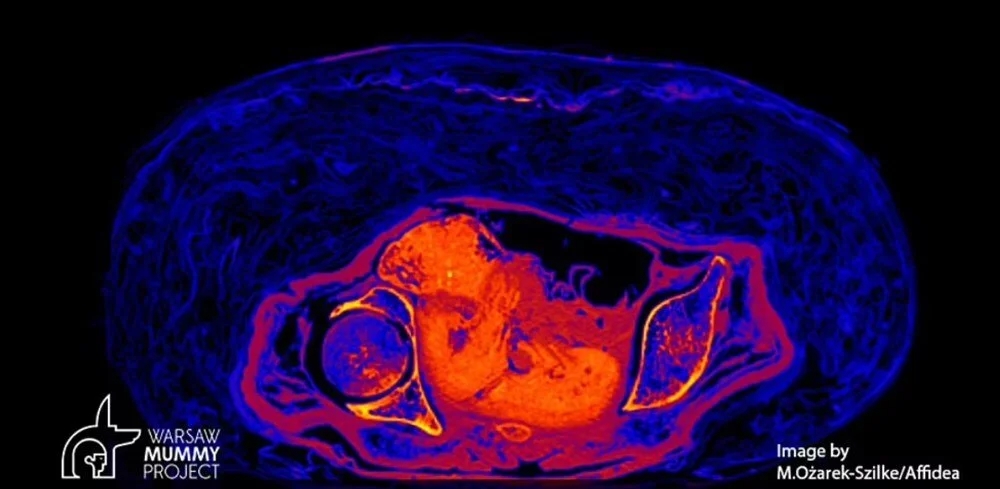

Yeni teknolojiler kullanan bilim insanları, "Gizemli Kadın" olarak adlandırılan bir Mısır mumyasının karnındaki fetüsü ortaya çıkardı. Bebeğin 2 bin yıl boyunca bozulmadan kaldığını açıklayan uzmanlar, mumyanın ölüm nedeni hala beliryemediklerini, ancak gerçek bir insanlık trajedisine ışık tuttuklarını söyledi. Peki bebek yıllarca bozulmadan nasıl günümüze kadar geldi? İşte haberin detayları...

Mısırlı bir mumyanın karnında bulunan bir fetüsün, kadının vücudunun çürürken asitlenmesi nedeniyle 2 bin yıldan uzun bir süre boyunca korunduğu belirtildi.

Kadın mumyası ve doğmamış çocuğu hakkındaki çalışma, Polonya'nın Varşova Üniversitesi'nden arkeolog ve paleopatolog Marzena Ożarek-Szilke ve meslektaşları tarafından üstlenildi.